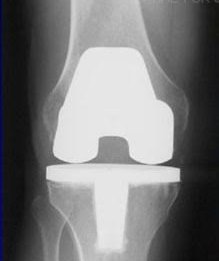

If your doctor wants to treat the osteoarthritis in the knee with surgery, the options are arthroscopy, osteotomy, and arthroplasty.

• Joint replacement surgery, or arthroplasty, is a surgical procedure in which joints are replaced with artificial parts made from metals or plastic. The replacement could involve one side of the knee or the entire knee. Joint replacement surgery is usually reserved for people over age 50 with severe osteoarthritis. The surgery may need to be repeated later if the prosthetic joint wears out after several years. But with today’s modern advancements, most new joints will last over 20 years. The surgery has risks, but the results are generally very good.